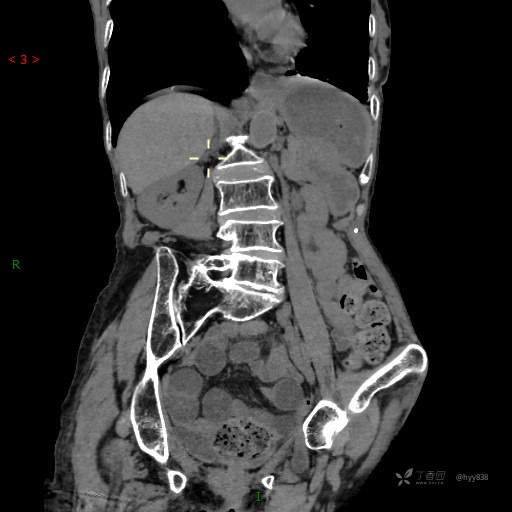

腹部CT平扫